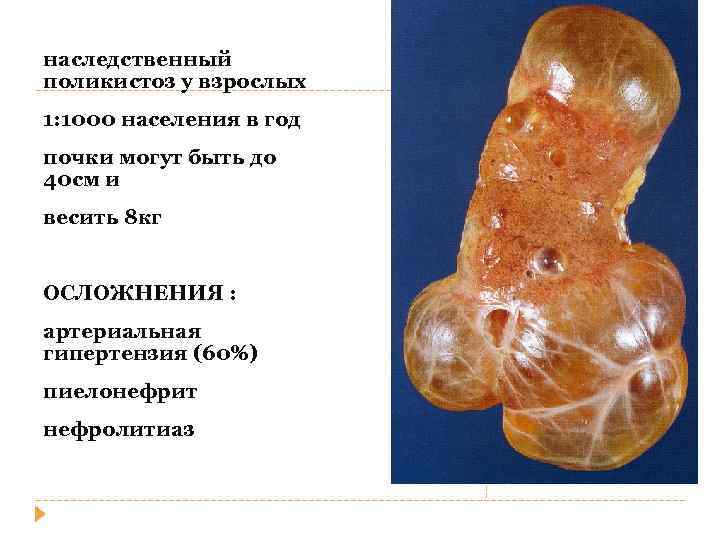

наследственный поликистоз у взрослых 1: 1000 населения в год почки могут быть до 40 см и весить 8 кг ОСЛОЖНЕНИЯ : артериальная гипертензия (60%) пиелонефрит нефролитиаз